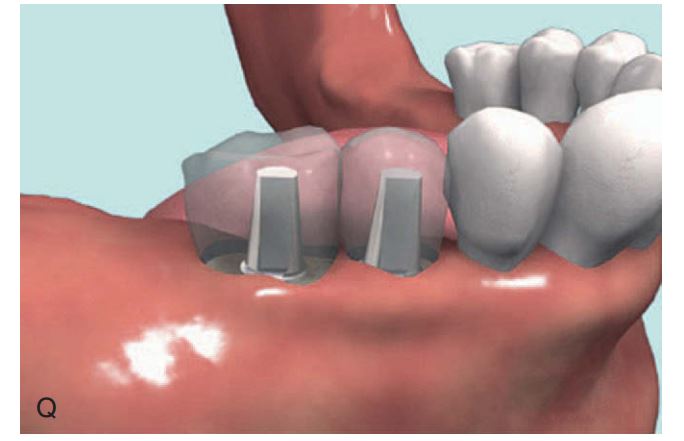

Dụng cụ hướng dẫn định vị Implant

Giúp xác định đúng vị trí đặt Implant và lựa chọn đường kính Implant tối ưu nhất (H2.18). Bộ hướng dẫn ITT gồm có:

– Tấm Titan, giúp hướng dẫn đường kính và vị trí của 1 – 2 Implant.

– Pin đo đạc có phần mở rộng, giúp hướng dẫn đường kính và vị trí Implant ở bệnh nhân không răng.

– Pin song song, để xác định độ song song của Implant.

– Cán của tấm Titan, giúp cầm nắm và đặt tấm Titan vào trong miệng 1 cách an toàn.